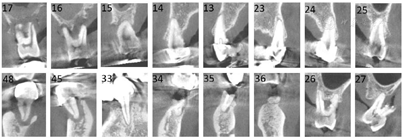

种植修复后1、2、4年随访X线全颌曲面体层片显示种植体周围骨结合良好(图13A~C),患者对修复体美观及咀嚼功能效果满意。修复后6年(2022年8月)随访X线全颌曲面体层片及根尖片显示种植体周骨结合良好,上前牙区种植体颈部骨吸收约1 mm(图13D、图14)。取下上下颌义齿,清理义齿组织面滞留菌斑,清洁复合基台并检查基台中央螺丝稳定,清洁义齿组织面,戴回上下颌义齿(图15)。患者口腔卫生宣教,指导正确刷牙,使用冲牙器冲洗义齿与牙龈间缝隙,嘱6个月复查、维护。